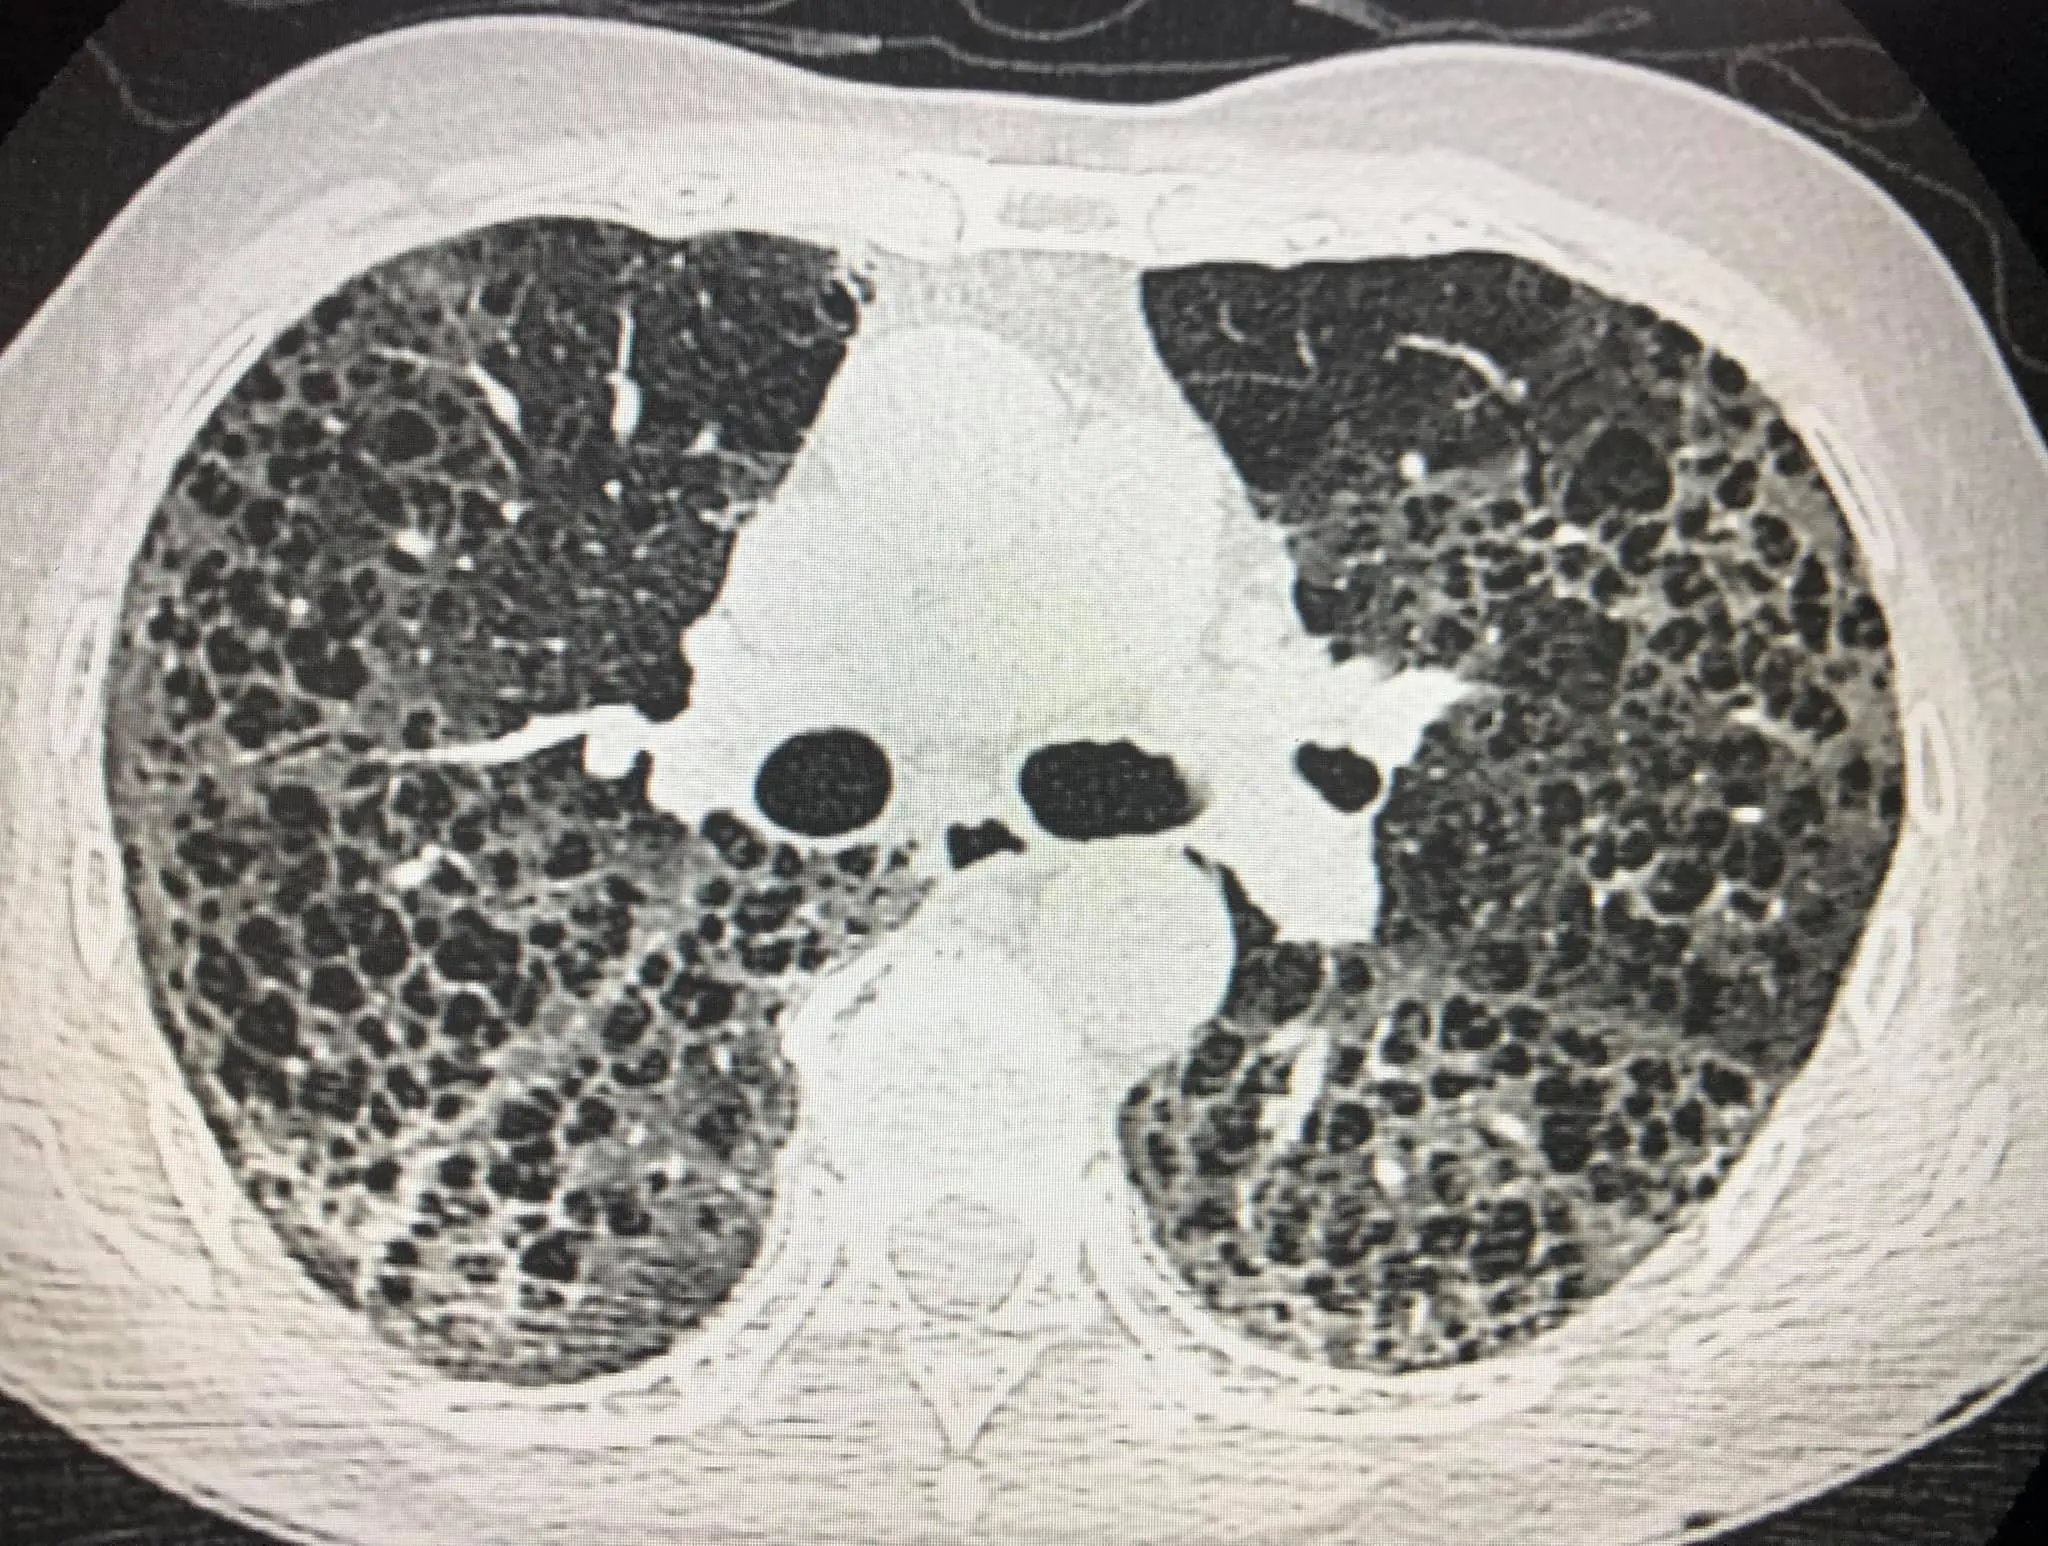

ผู้ป่วยชายไทยอายุ 80 ปี ปกติแข็งแรงดี ไม่มีประวัติป่วยเป็นโรคปอด ไม่สูบบุหรี่ เมื่อวันที่ 16 เมษายน 2564 ป่วยเป็นโรคโควิด-19 โดยลูกเป็นคนนำเชื้อมาให้ผู้ป่วยและคนในครอบครัวรวมทั้งหมด 7 คน เข้านอนรักษาในโรงพยาบาลด้วยปอดอักเสบรุนแรง เอกซเรย์ปอดมีฝ้าขาวทั้ง 2 ข้าง (ดูรูป) ทำคอมพิวเตอร์สแกนปอดพบเนื้อเยื่อปอดอักเสบรุนแรง มีทั้งฝ้าขาว รอยโรคเหมือนร่างแห และลักษณะผิดปกติคล้ายรังผึ้ง กระจายทั่วปอด (ดูรูป) ผู้ป่วยได้รับการรักษาเต็มที่ โชคดีที่ไม่ต้องใส่เครื่องช่วยหายใจ ต้องใช้ออกซิเจนมากถึง 10 ลิตร/นาทีตลอดเวลา นอนในรพ.ถึงวันที่ 22 พฤษภาคม 2564